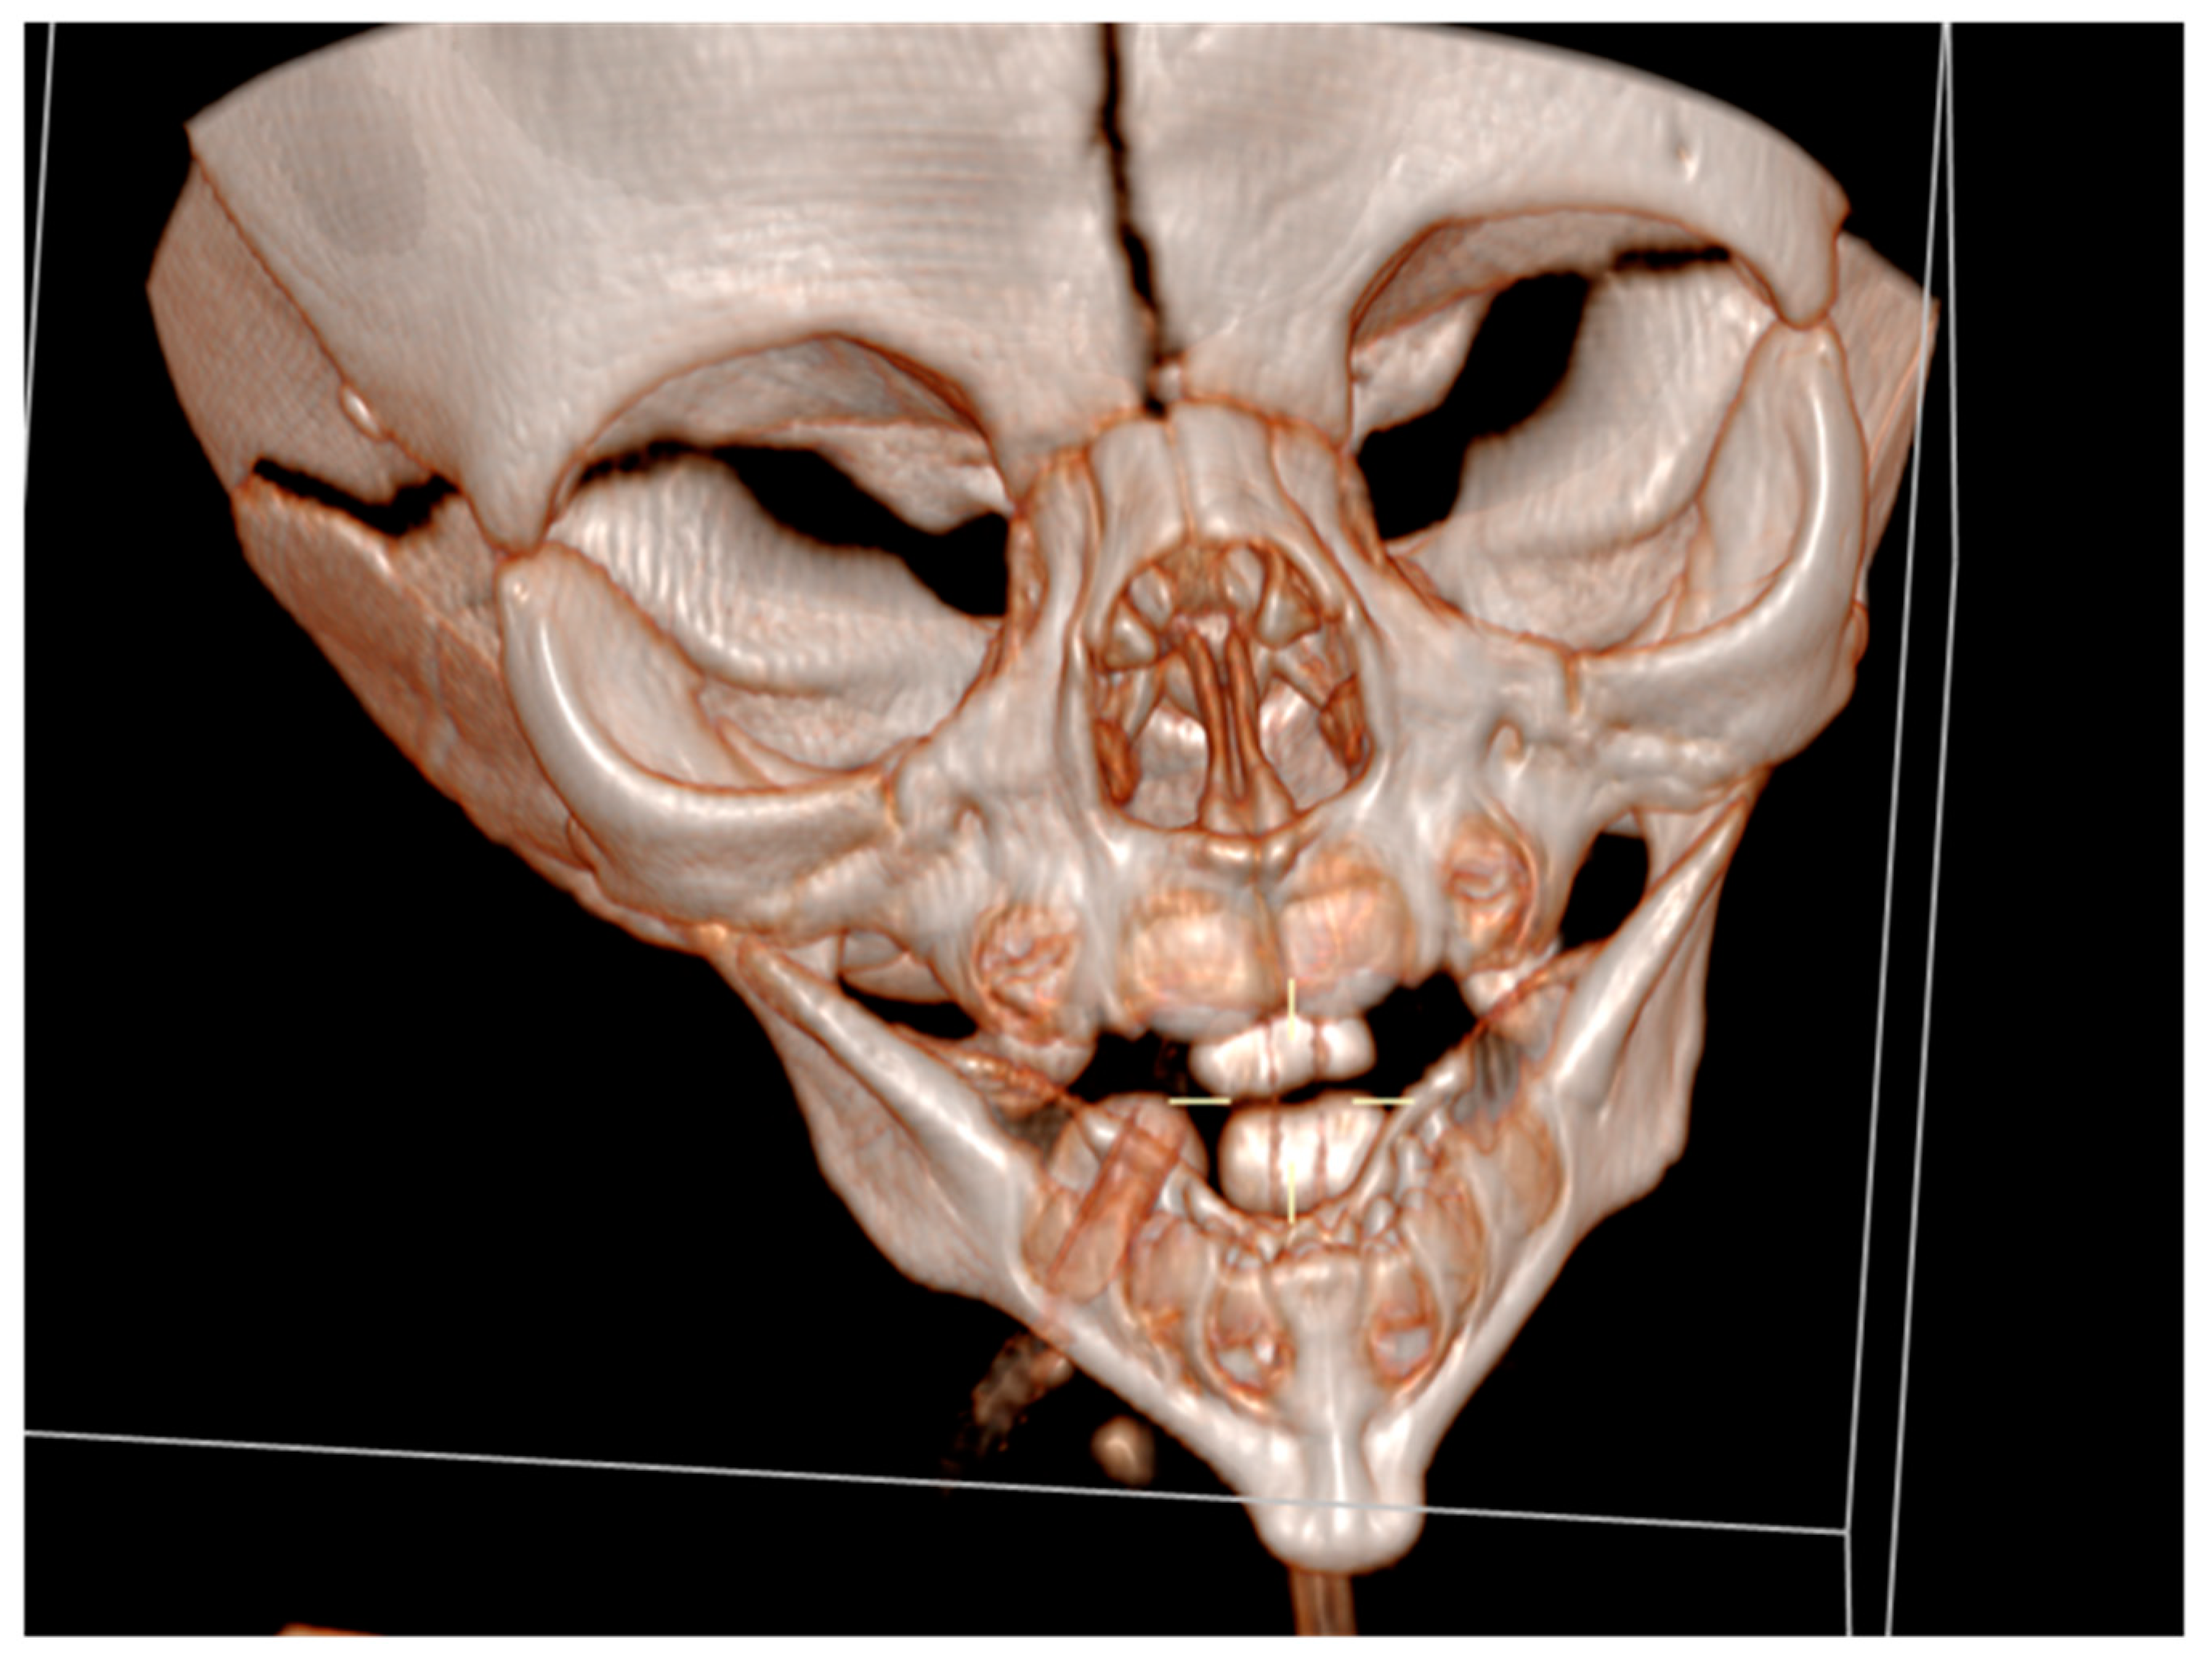

It had underdeveloped body region and pointed chin. Only three tooth germ of the lower frontal teeth was present, that was only one lower medial incisor and two lateral incisors. Temporomandibular joints were normal (Figure 4).

Figure 4. Temporomandibular joints is normal.